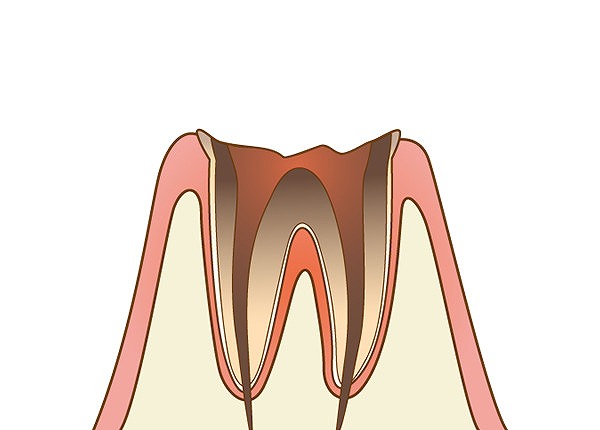

C4:歯根に達したむし歯

歯を支える歯槽骨に接する歯根にまでむし歯菌に侵されています。歯ぐきの上に現れている歯冠部分はかなりの部分が溶けてなくなっています。歯髄にある神経が死んでしまっているため、痛みが治まっていることもありますが、歯根部分が膿んでくると強い痛みが現れます。

歯を支える歯槽骨に接する歯根にまでむし歯菌に侵されています。歯ぐきの上に現れている歯冠部分はかなりの部分が溶けてなくなっています。歯髄にある神経が死んでしまっているため、痛みが治まっていることもありますが、歯根部分が膿んでくると強い痛みが現れます。

抜歯しなければいけないケースが多くなり、入れ歯やインプラント、ブリッジなどの治療で補う必要があります。